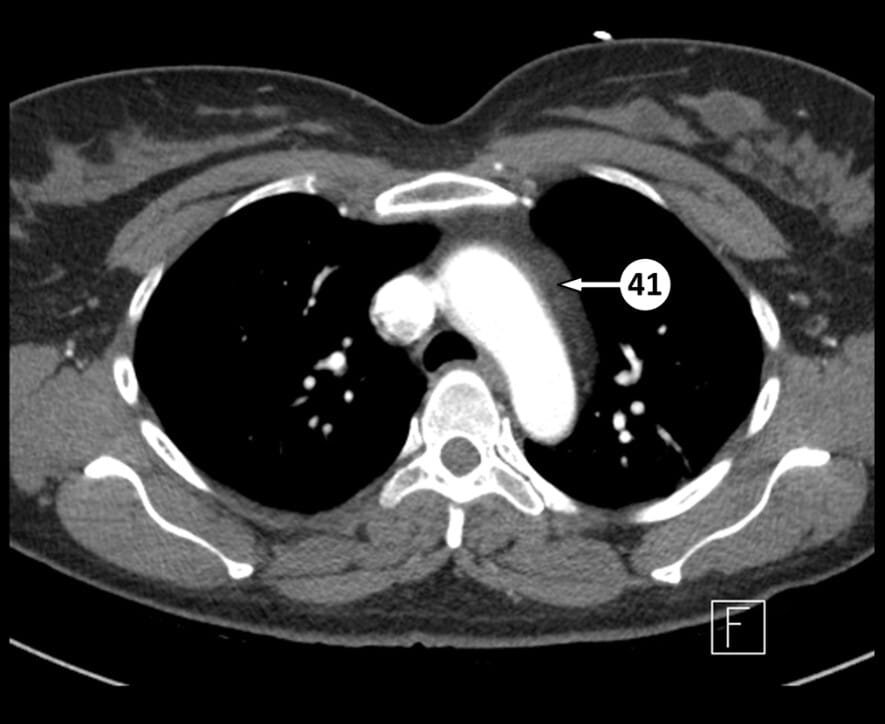

41. mediastinal fat